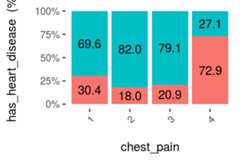

Since the variable to predict ishas_heart_disease, it appears something interesting, to have a heart disease is more correlated tothal=3 than to valuethal=6.

Same analysis for variablechest_pain, a value of 4 is more dangerous than a value of 1.

And we can check it with other plot:

cross_plot(heart_disease,input ="chest_pain",target ="has_heart_disease",plot_type ="percentual")

Figure 1.17: Visual analysis using cross-plot

The likelihood of having a heart disease is 72.9% if the patient haschest_pain=4. More than 2x more likely if she/(he) haschest_pain=1 (72.9 vs 30.4%).